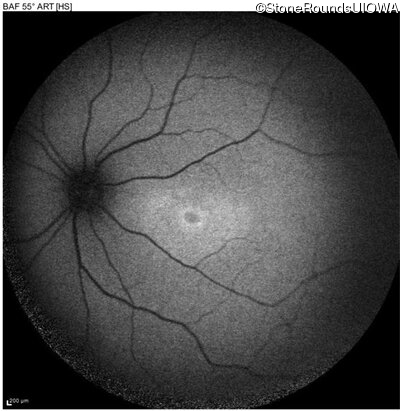

Blue Autofluorescence - Left - 20/50 -1

Exemplar